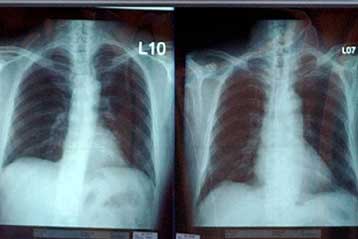

Αθήνα: Αμερικανοί ερευνητές, χρησιμοποιώντας γενετικές τεχνικές, ανακάλυψαν μια μέθοδο να εντοπίζουν εκείνους τους καπνιστές, που αντιμετωπίζουν τον μεγαλύτερο κίνδυνο να εμφανίσουν καρκίνο των πνευμόνων.